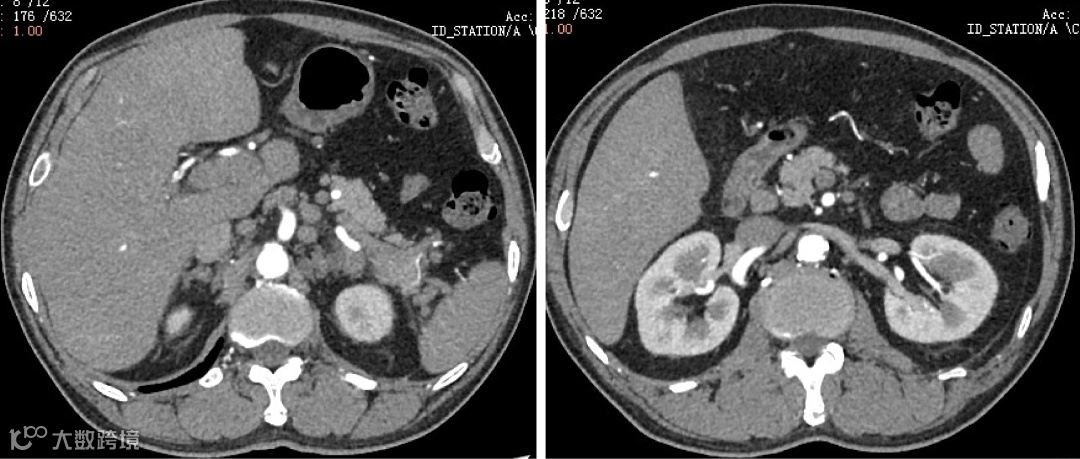

肝门区、胃小弯侧、腹膜后、腹主动脉旁多发淋巴结,部分肿大、融合,肝内多个弱强化结节,脾脏弱强化灶